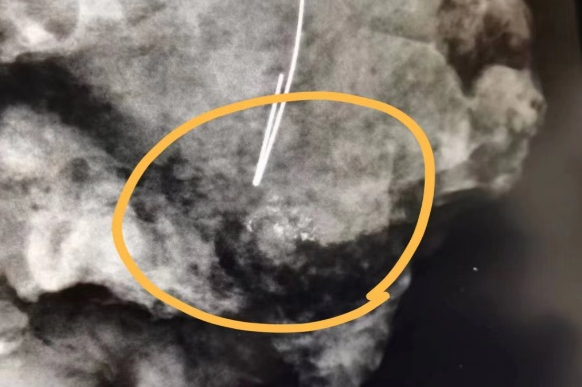

患者通过钼靶检查,诊断为右乳钙化。经过与患者及家属沟通,榆林市星元医院乳腺疾病诊疗中心主任医师张小龙、副主任医师李军为患者进行数字钼靶3D定位引导下乳腺钙化灶切检术,精准切除约3×3×2cm的钙化灶,手术过程顺利,出血量少,术后患者安返病房。

可疑钙化灶

计算机系统立体定位

引导穿刺针植入带钩导丝

手术精确切除导丝

定位病灶

X线拍片保证手术切除和导丝放置准确性